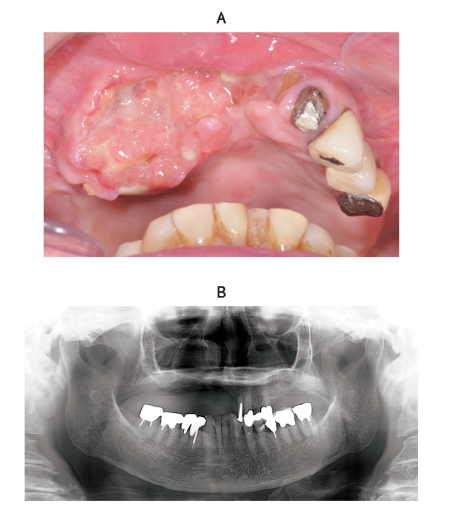

56 歳の女性。下顎左側臼歯部の痛みと歯の動揺を主訴として来院した。 2 か月

前から疼痛を自覚し、次第に動揺してきたという。下顎左側臼歯部に 42 × 20 mm

大の腫瘤を認め、生検の結果は扁平上皮癌であった。FDG-PET/CT で遠隔転移を

認めなかった。初診時の口腔内写真(別冊No. 31A)、エックス線画像(別冊No. 31

B)及び FDG-PET/CT(別冊No. 31C)を別に示す。

TNM 分類(UICC2017)はどれか。 1 つ選べ。

解答:d

解説:

T:癌の広がり

N:リンパ節転移 N0:なし N1:3cm以下。一つのリンパ節に転移。癌と同側 N2:6cm以下。2つ以上のリンパ節の転移。癌と同側 N3:6cm以下。リンパ節の転移。癌と同側と反対側に。

M:遠隔転移

下顎左側臼歯部に 42 × 20 mm⇒4cmをこえているのでT4a

遠隔転移なし⇒M0

FDG-PET⇒癌の広がり具合、転移場所が分かる検査。今、左側(癌と同じ側)に複数リンパ節転移しているのが分かる。そして、6cm以下なのでN2b

T4bほど浸潤していない。